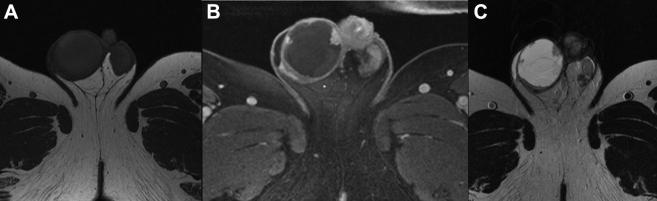

Serous borderline tumor (SBT) of the testis is a rare, ovarian epithelial-type tumor of the testis. We present a case of SBT after radical orchiectomy in a 59-year-old man who had 3-month progressive enlargement of his right hemi-scrotum, negative testicular tumor markers and scrotal ultrasound equivocal for malignancy. Magnetic resonance imaging (MRI) of the pelvis was obtained to aid with evaluation and showed marked hyperintensity on T2-weighted images with frond-like nodular peripheral enhancement within right testis mass. These distinct MRI findings can help clinicians differentiate SBT from other testis tumors. Relapse has not been observed in 8 years of follow-up.

睾丸浆液性交界性肿瘤(SBT)是一种罕见的睾丸卵巢上皮型肿瘤。我们报告一例59岁男性患者,在根治性睾丸切除术后发生SBT。该患者右侧半阴囊进行性肿大3个月,睾丸肿瘤标志物阴性,阴囊超声检查对恶性肿瘤的判断不明确。盆腔磁共振成像(MRI)用于辅助评估,结果显示右侧睾丸肿块在T2加权图像上呈明显高信号,周边有叶状结节样强化。这些独特的MRI表现有助于临床医生将SBT与其他睾丸肿瘤区分开来。随访8年未观察到复发情况。